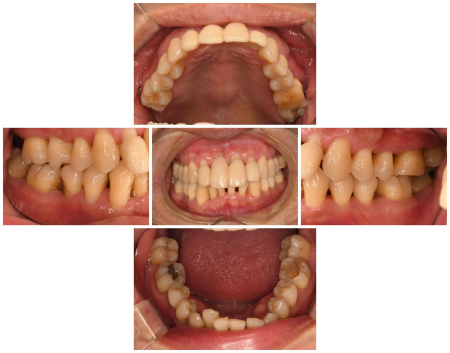

治療前

拝見したところ、上の前歯数本に出血と揺れが生じていました。

特に右上の前歯(中切歯/1番)は揺れが著しく、他院で応急処置がされており、口腔内で使用できる接着剤「スーパーボンド」で固定された状態でのご来院でした。

歯ぐきの検査やレントゲン撮影を行った結果、若くして歯を支える組織に炎症が起こる「若年性歯周病」が全体的に進行した状態と診断しました。

歯の表面や歯ぐきの内側には、歯周病の原因となる細菌の塊「プラーク」や、プラークが硬く石灰化した「歯石」の付着が認められました。